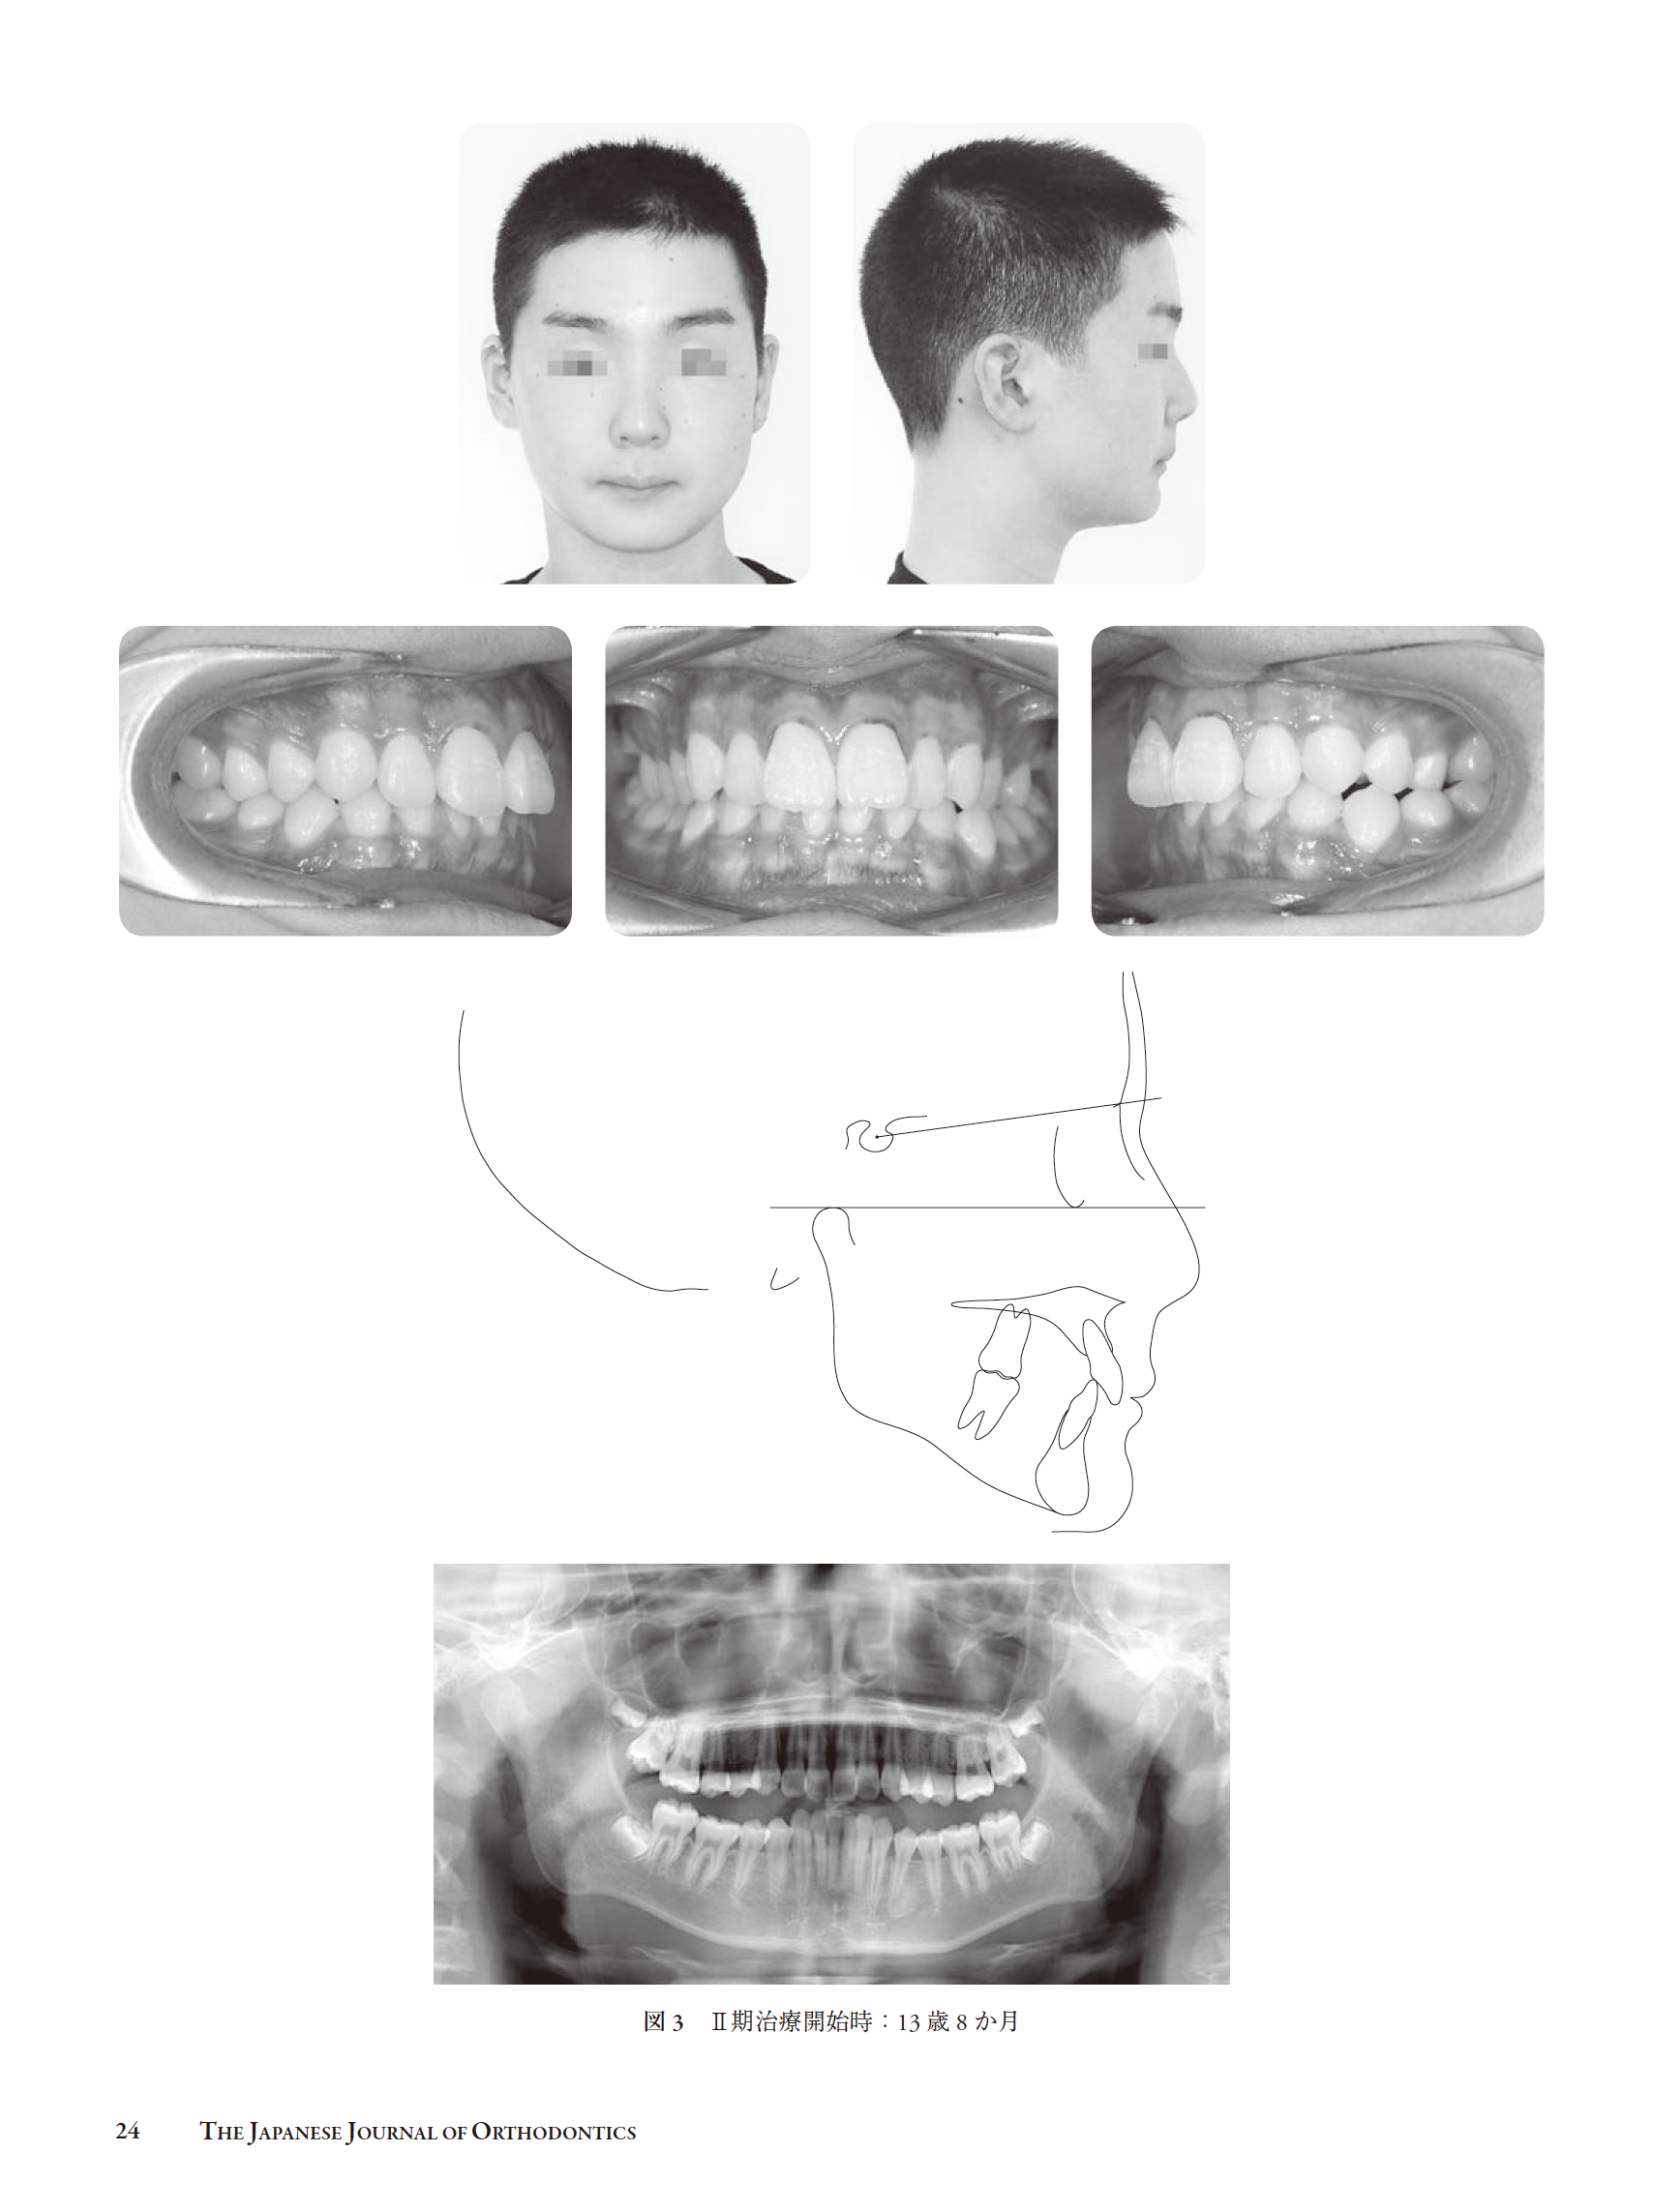

早期治療を行なった上突咬合の一治験例(和島)